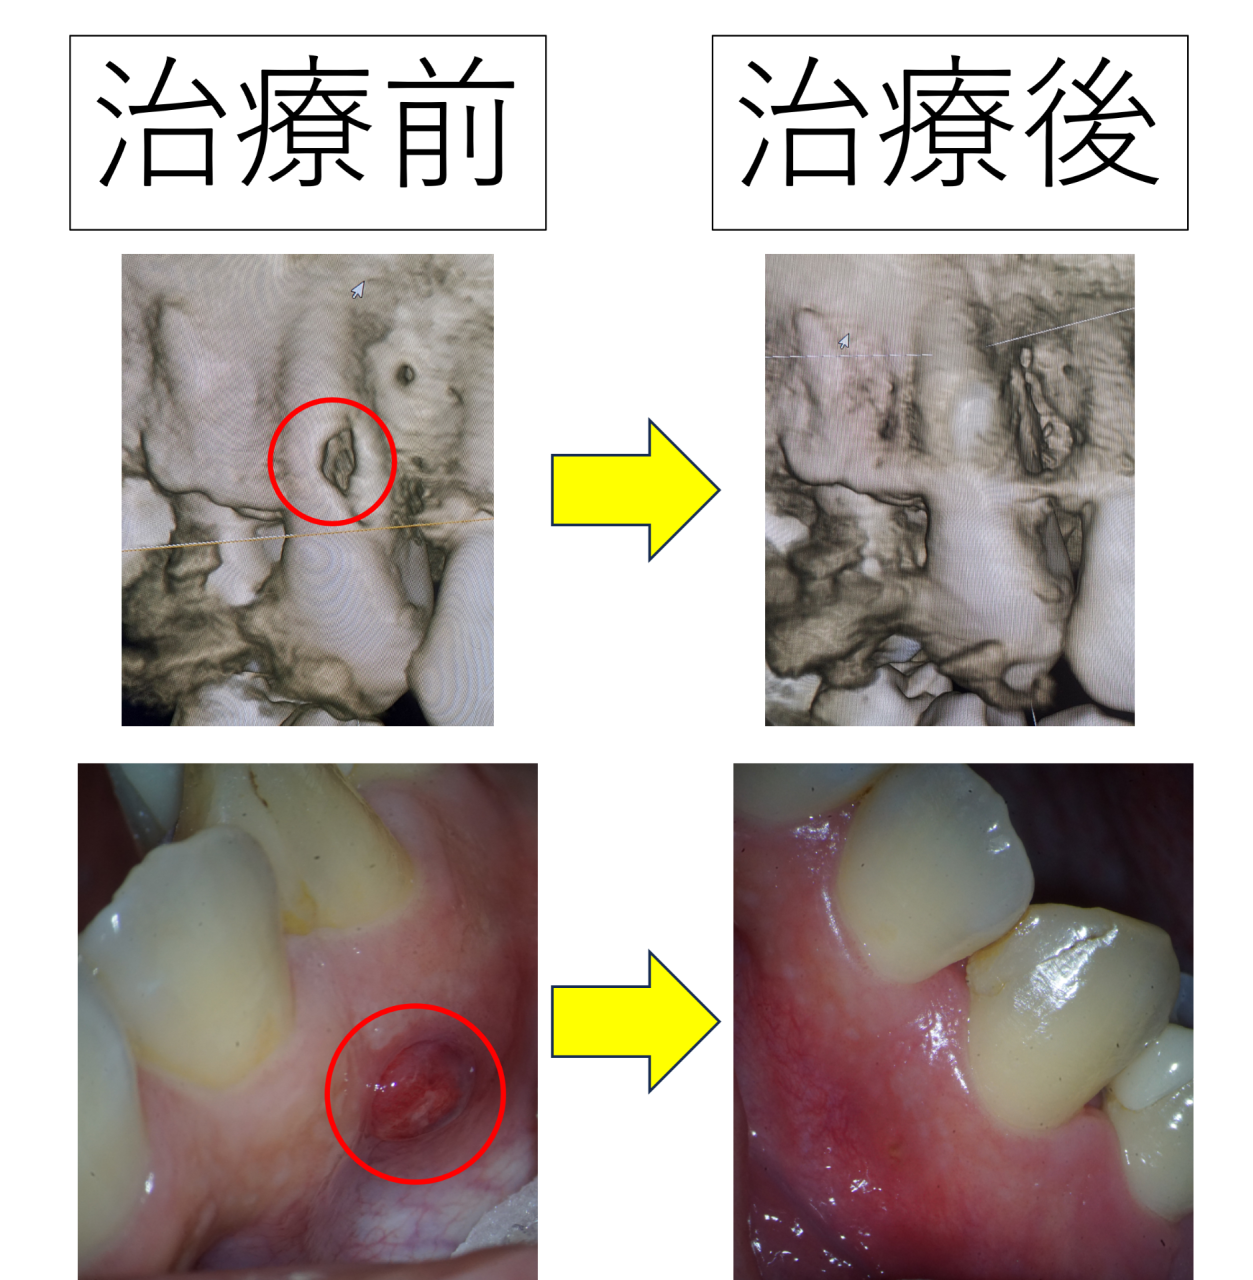

歯茎の炎症や菌の増殖などで「歯が痛む」「腫れが気になる」「食べているとしみる」などの症状を感じたことはないでしょうか。歯周病の治療では、まずは顕微鏡検査で歯を大きく確認しながら、どれくらいの状態なのか、歯茎の中にまで菌が増殖していないかなど、状況を確認してから治療を進めてまいります。

みつおデンタルクリニックでは、マイクロスコープ(顕微鏡)やCTなどのレントゲンによる精密な検査を行っております。そのため、最近では、セカンドオピニオンを求めて来院される患者様が増えてきました。…

患者様の歯の状態や性質などをしっかりと見極め、それぞれの患者様に合う最適な治療方法をご提案しております。例えば、症状が中等度から重度になるにつれて、また歯茎の奥や歯の奥など、見えにくくなる場所の治療になるほど、歯周病の治療には高度な技術や経験、器材が必要になってきます。そのため、治療は歯科衛生士でも担当できますが、高度な技術が必要な治療に関しては院長自らが責任を持って治療を実施します。一人ひとりの歯の健康をお守りできるよう、根本からの改善を目指す高技術な治療を丁寧に実施します。